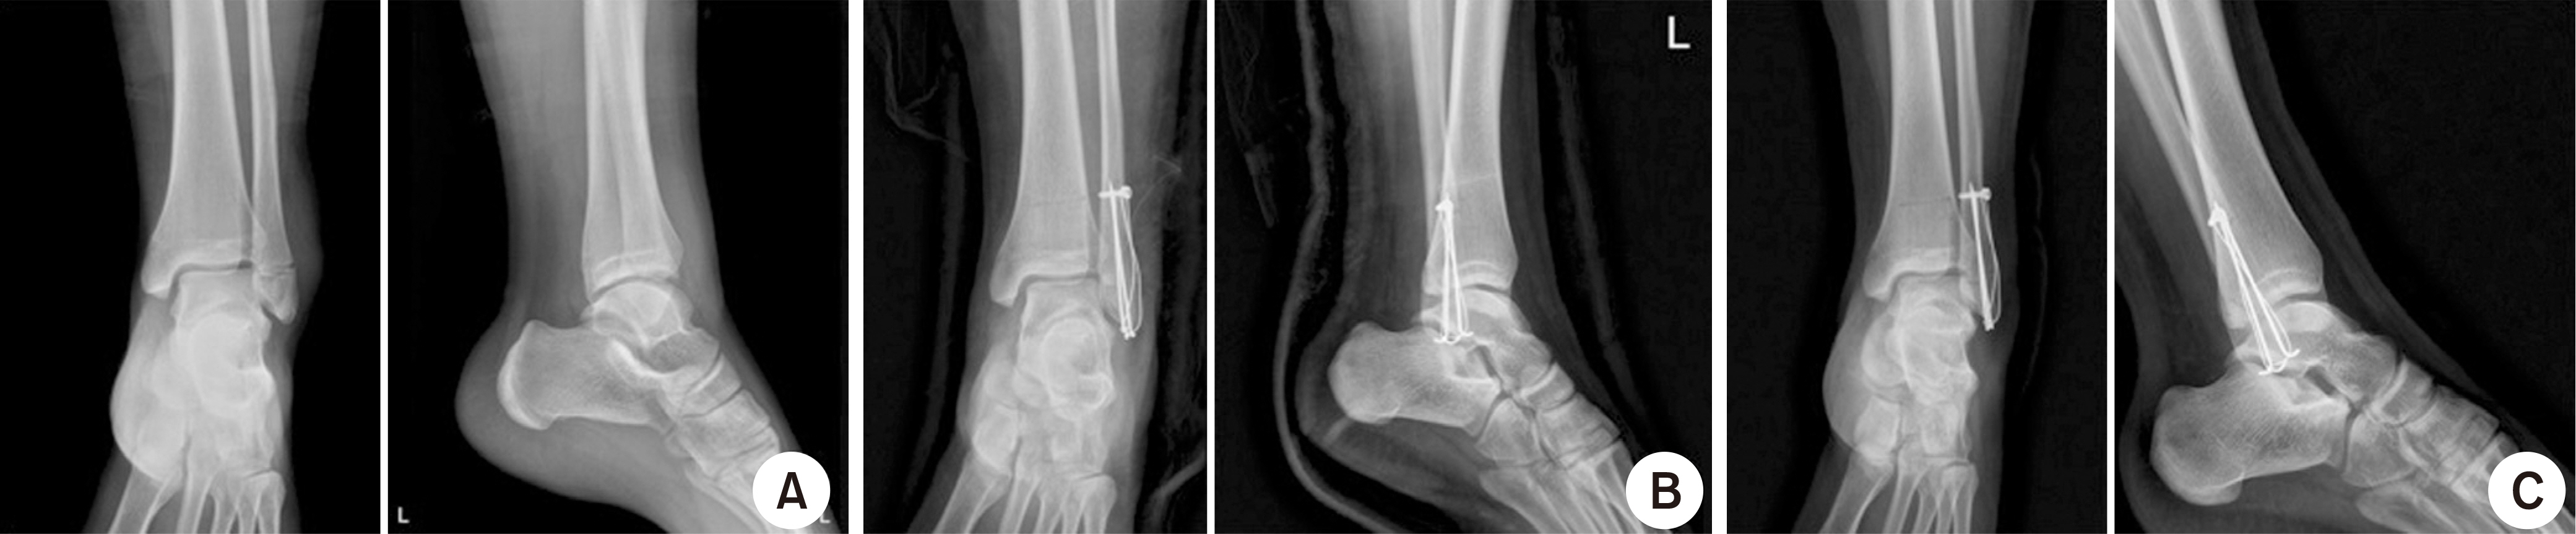

Fig. 2.

(A) A 32-year-old male patient was diagnosed with isolated lateral malleolar fracture according to the simple radiography. (B) Surgical fixation with the tension band wire on the postoperative radiography. (C) Bone-union was achieved within 12 months of surgery.